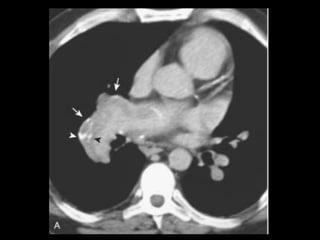

• 62.

Embolia Pulmonar Diagnóstico deembolia aguda na TC com contraste é baseado na visualização direta de falhas de enchimento parciais ou completas dentro das artérias pulmonares; Sinal da “rosca”; Sinal do “trilho de trem”; Outro sinal útil: formação de ângulos agudos com a parede vascular, a perda completa da opacificação e o aumento do diâmetro do vaso acometido.

• 70.

Embolia Pulmonar Tromboscrônicos: com frequência aparecem como defeitos de enchimento em forma de crescente ou laminares aderidos às paredes da artéria pulmonar; Calcificações podem estar presentes; Armadilhas: tempo de delay, volume de contraste, sangue não opacificado oriundo da veia cava inferior e do átrio direito( interrupção transitória de contraste);